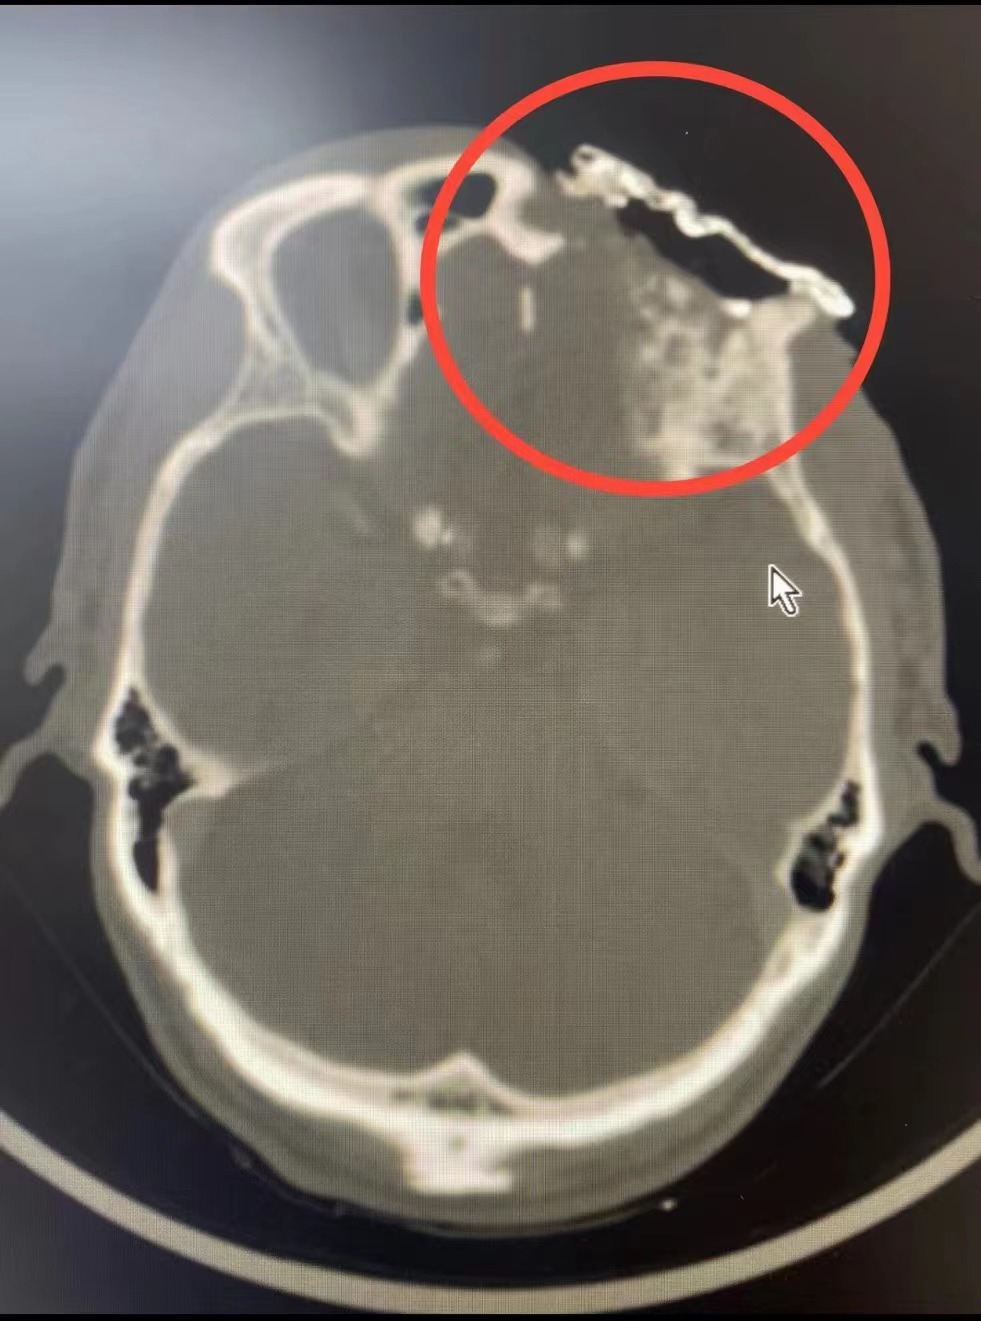

术前CT、MRI所示肿瘤

患者家属曾因陈伯年龄较大犹豫是否进行手术治疗,但手术为该类疾病的首选方案,为了尽量减轻陈伯及家属的顾虑,吕忠耐心详细地给他们讲解了手术的利与弊,最终患者及家属选择手术治疗。为了解决完整切除陈伯眼眶、前颅底、筛窦区肿瘤及封闭修复前颅底、筛窦、眼眶的问题,吕忠联合眼科、综合外科针对陈叔的病情及术前CT、MRI、喉镜等影像资料,对手术方案进行反复讨论和研究,最终选择眼眶基底细胞癌扩大切除(包括前颅底、眼眶、筛窦病灶)+游离股前外皮瓣转移修复。考虑到患者年龄较大,为了缩短手术时间降低手术麻醉风险,最终一边由吕忠团队负责切肿瘤,另一边由综合外科易广田主任团队同时制备股前外游离皮瓣,再由吕忠团队使用皮瓣修复切除肿瘤后的前颅底、鼻窦、眼眶区域皮肤软组织的缺损。经过充分的术前准备,专家团队如期为陈叔进行手术。凭借精湛而熟练的手术技巧及默契的团队配合,历经约3小时,手术顺利结束。术后在科室全体医护人员的精心护理下,陈伯恢复良好。